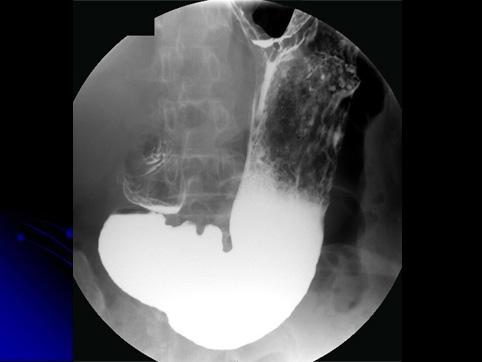

질환(병리주체)의 분류 양성 상피성종양/선종

부위(장기별) 위(부위)/전정

검사방법 X-P

종양의 육안분류 0형(표재형)/IIa형(IIa)

종양의 최대경(밀리미터) 20~24

다발종양(동일 장기) 유(동시성)